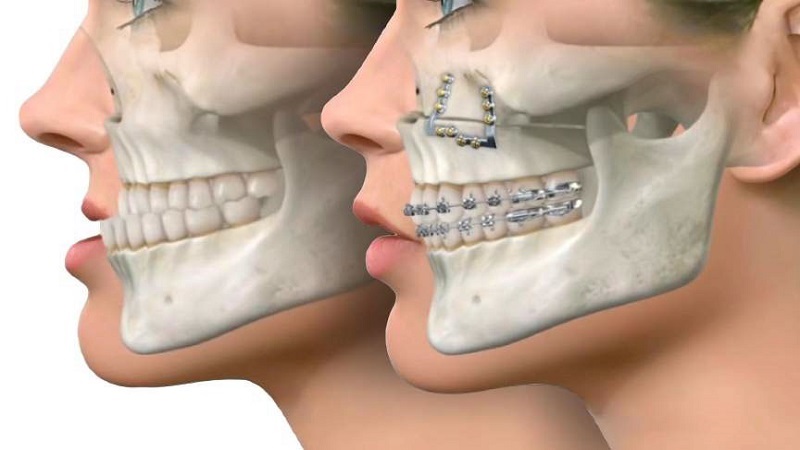

جراحی فک، که به عنوان جراحی ارتوگناتیک نیز شناخته میشود، به منظور اصلاح ناهنجاریهای ساختاری فک و صورت انجام میشود. این نوع جراحی میتواند به بهبود عملکرد جویدن، تنفس و زیبایی صورت کمک کند. با این حال، بهبودی پس از جراحی فک یک فرآیند پیچیده است که تحت تأثیر عوامل مختلفی قرار دارد، از جمله سن بیمار، وضعیت سلامت عمومی و مصرف داروها. یکی از مسائلی که در این زمینه به آن توجه شده است، تأثیر داروهای ضد بارداری هورمونی بر روند بهبودی بعد از جراحی فک است. در این مقاله از سایت دکتر بهنام خرمی (جراح بینی اصفهان _ جراح فک اصفهان)، به بررسی این تأثیرات خواهیم پرداخت.